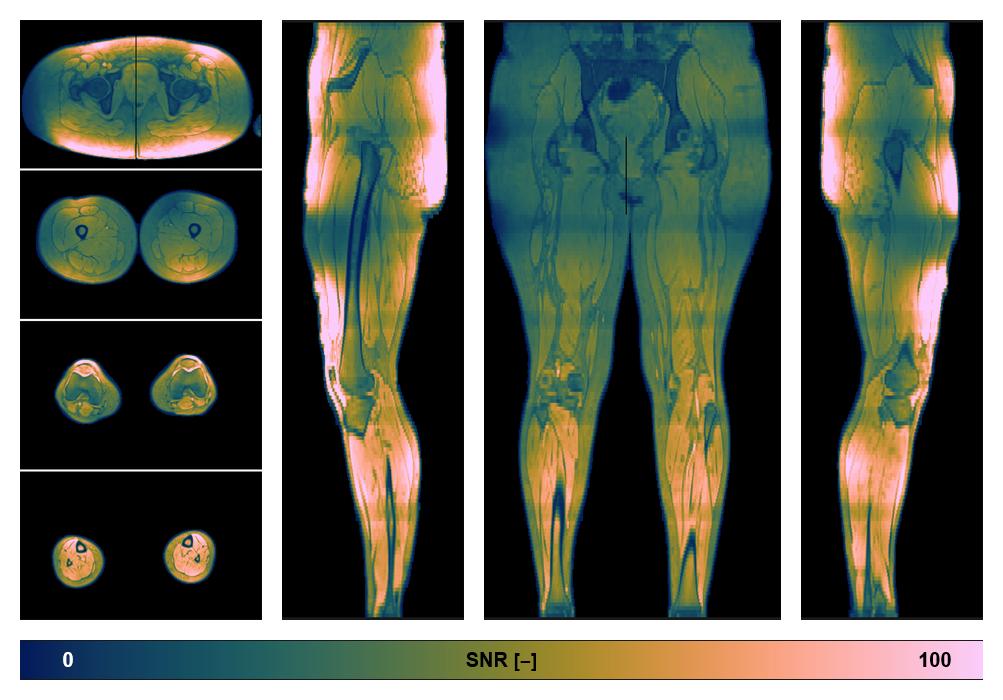

• SNR distribution

The SNR distribution of the dixon data.